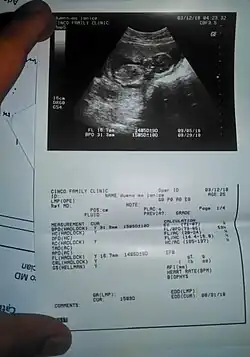

Obstetricia

Esta técnica diagnóstica también se conoce como ecografía o sonografía.[16]

La máquina de ultrasonido tiene cristales piezoeléctricos que al ser estimulados por electricidad vibran produciendo ondas sonoras de alta frecuencia que hacen eco en las estructuras corporales retornando a los cristales que nuevamente estimulados ahora por ultrasonido producen pequeños voltajes que son procesados de acuerdo a su intensidad y tiempo de retorno mediante un computador que tiene un convertidor de barrido digital creando así las imágenes. A diferencia de los rayos X, en este examen no se presenta ninguna exposición a la radiación ionizante y no se ha detectado ningún riesgo utilizado con los aparatos apropiados para diagnóstico. En la actualidad existen ecógrafos del tamaño de un celular que pueden ser empleados para diagnóstico inmediato.[17]

Las frecuencias típicas utilizadas para aplicaciones en abdomen pueden ir desde 2,0 MHz a 5,0 MHz mientras que para regiones como mama, músculo-esqueléticas, tiroides, etc., las frecuencias pueden oscilar entre 8,0 MHz a 16,0 MHz. Se utilizan frecuencias más altas para medición de estructuras muy pequeñas y superficiales